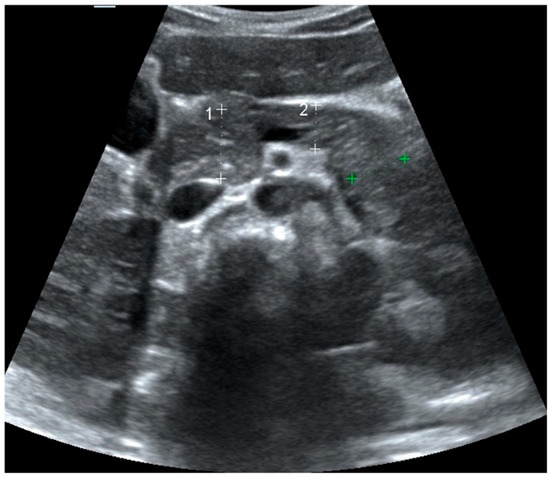

2.2. Pancreas Ultrasonography: Pancreatic Size and Echogenicity